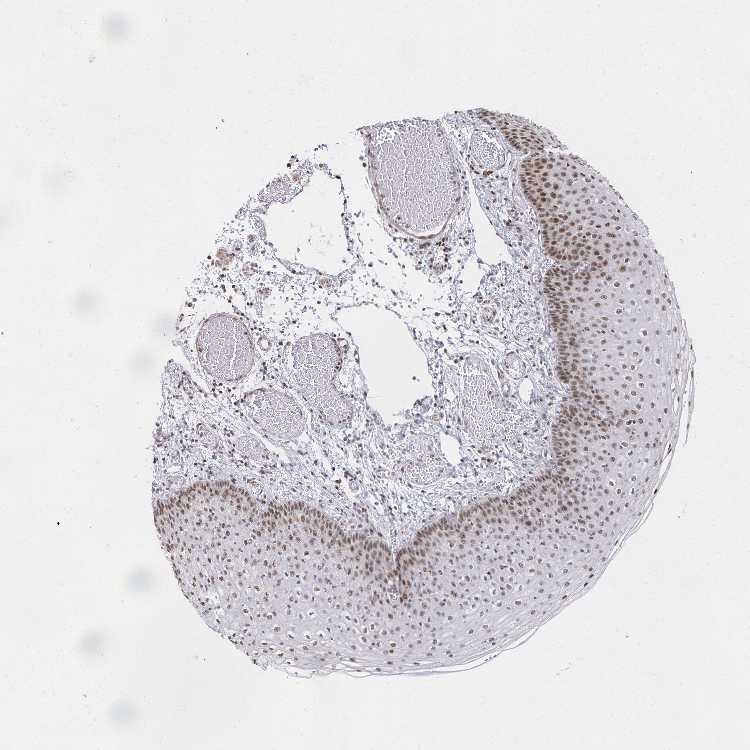

ESOPHAGUS - Antibody stainingi

Antibody staining in the annotated cell types in the current human tissue is reported as not detected, low, medium, or high, based on conventional immunohistochemistry profiling in selected tissues. This score is based on the combination of the staining intensity and fraction of stained cells.

Each image is clickable and will lead to virtual microscopy that enables deeper exploration of all samples and also displays staining intensity scores, fraction scores and subcellular localization as well as patient and tissue information for each sample.

Antibody HPA061626

Squamous epithelial cells High